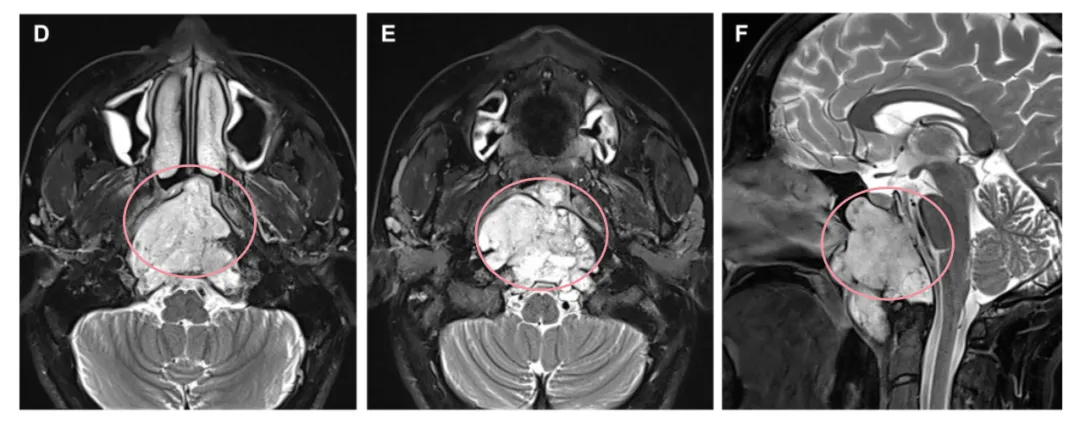

一名48岁女士因右侧展神经麻痹来到福教授所在科室就诊。术前MRI显示一个大的斜坡脊索瘤,延伸到岩尖、海绵窦、髁突和颈静脉孔、蝶窦和咽后间隙,侵犯至硬膜内(图1D-1F)。

▼D、E术前轴向和F矢状t2加权MRI